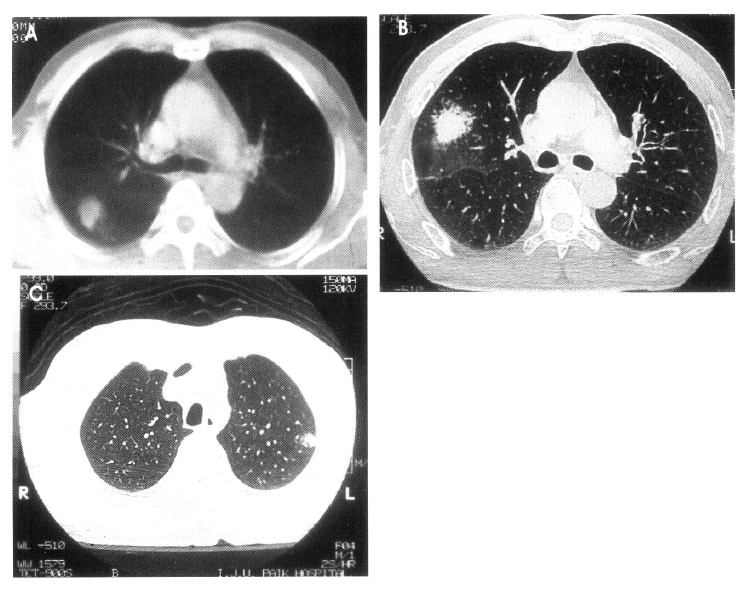

Serial chest radiography (Figure 2A, 2B) and high resolution computed tomography (Figure 3A, 3B, 3C) showed that the pulmonary nodules and patchy densities migrated to other sites and changed in shape and size daily. On the second day of admission, the patient underwent fiberoptic bronchoscopy that revealed no endobronchial lesion. The bronchoalveolar lavage (BAL) fluid had cell proportions of 45% macrophage 15% lymphocytes, 15% neutrophils, and 25% eosinophils (Figure 4). The BAL fluid was negative for bacterial, acid-fast bacilli, and fungi. A transbronchial lung biopsy was performed at the right middle lobe. Microscopy of the lung tissue showed eosinophilic infiltration (Figure 5). Abdominal ultrasound revealed no specific abnormalities except mild splenomegaly. On the ninth day of admission, migrating nodular densities on chest radiographs decreased and then disappeared dramatically following oral praziquantel therapy (Figure 6). Blood eosinophilia consequently decreased and normalized. There was no evidence of recurrence after one year of follow-up.

Figure 3.

Outside chest CT scan (A) and follow-up chest CT scan (B, C) show migrating pulmonary nodules.